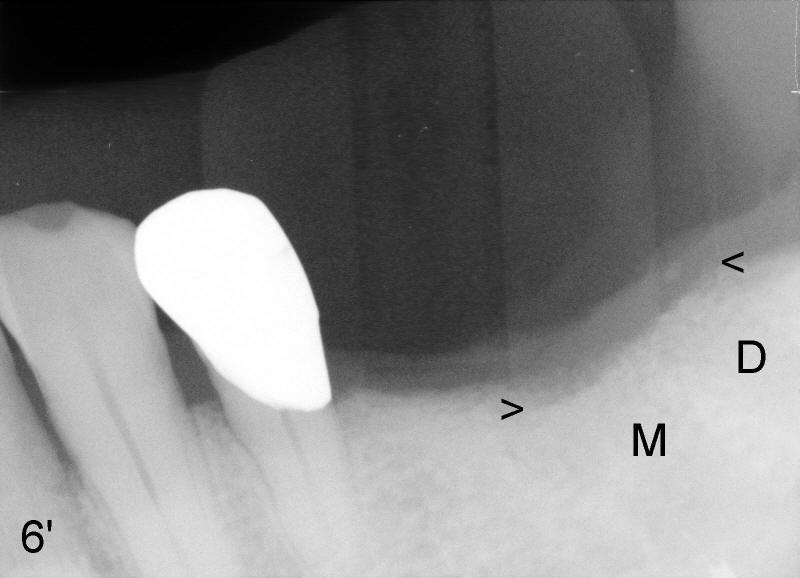

Mr. Lip returns to clinic for #30 and 31 implant placement. At the time of impression, there is no sign of gingival swelling around the tooth #19 (Fig.1: >; although the tooth has suspected root fracture). The patient requests keeping this affected tooth as long as possible while #30,31 implants are being placed and restored. This is not the case at the appointment of implant placement on the other side (Fig.1': *). There is localized gingival erythema and edema at the ML line angle. It appears that the treatment plan should be changed: the number of implants to be placed should be reduced from two to one and the infected tooth should be extracted to decrease the chance of implant infection. These two procedures are intended to be done at the same time so that bone harvested from #30 implant osteotomy (Fig.2) can be saved (Fig.2': < in dapen dish) and grafted in #19 sockets (Fig.3', 4'), particularly in the mesial one with severe bone loss due to root fracture.

Unfortunately, there is bone resorption around the implant 3 months postop (Fig.6: >, as compared to Fig.4). Granulation tissue is present over the implant (Fig.7 *). The patient complains occasional pain and swelling after implant placement. Bone resorption is confirmed after removal of granulation tissue around the implant (Fig.8 *). After acid etch, Endogain (Fig.9 *, Straumann) is placed around the implant (P: healing plug). Flaps are approximated with 4-0 plain gut suture. Collagen membrane should have been used. Amoxicillin is prescribed, but the patient does not take it. It appears that bone graft to the sockets of #19 helps form an apparently continuous bone plate at the alveolar crest over the mesial (M in Fig.6') and distal (D) sockets, as compared to Fig.4'.